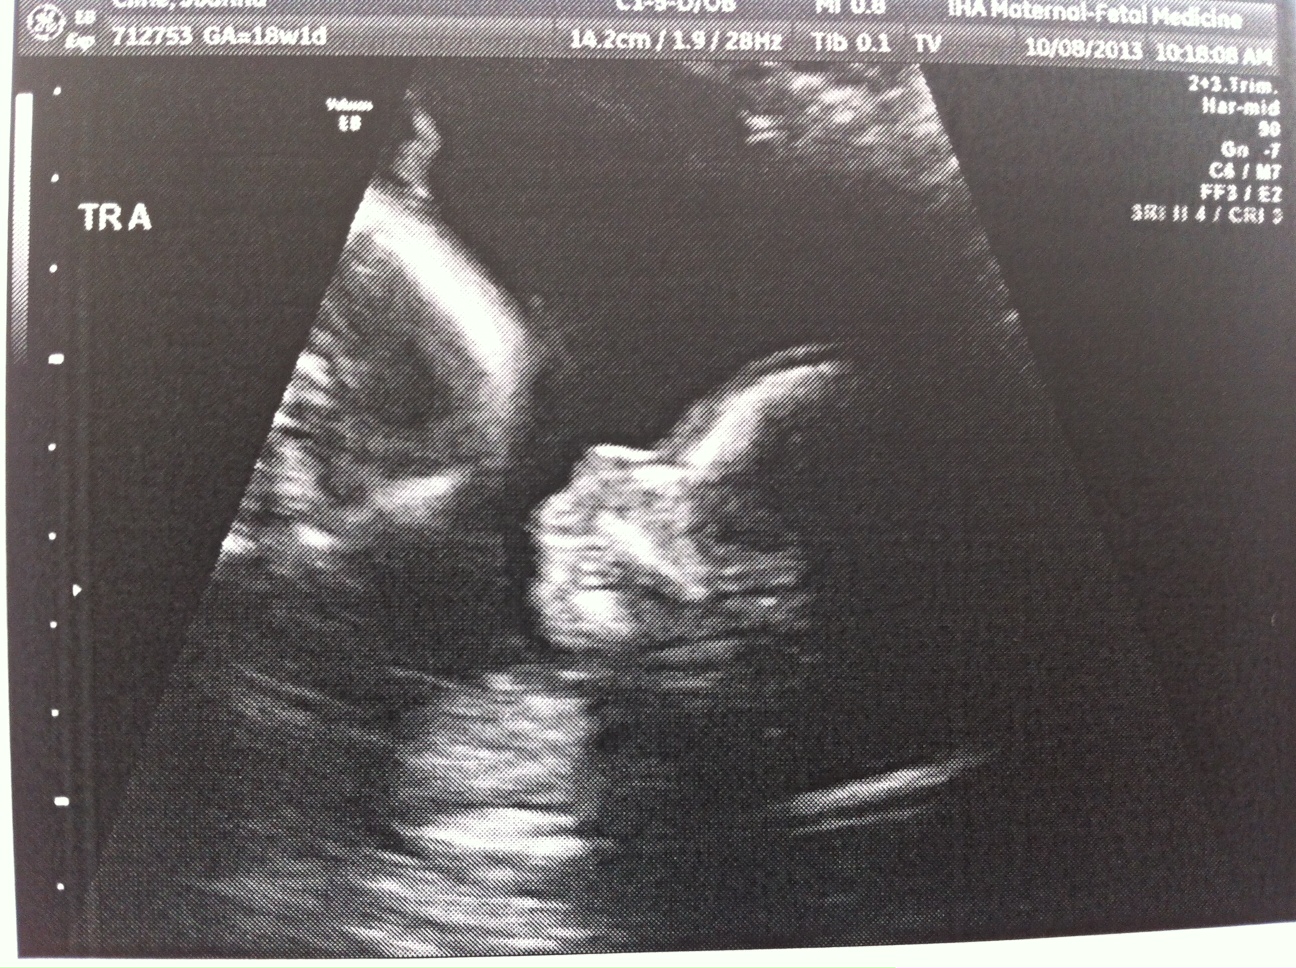

Everything still looks great. The triplets are growing but we won’t have another growth scan until my 22wk appointment. Heart beats look good and it’s clear they’re getting bigger (Today’s pictures attached.)